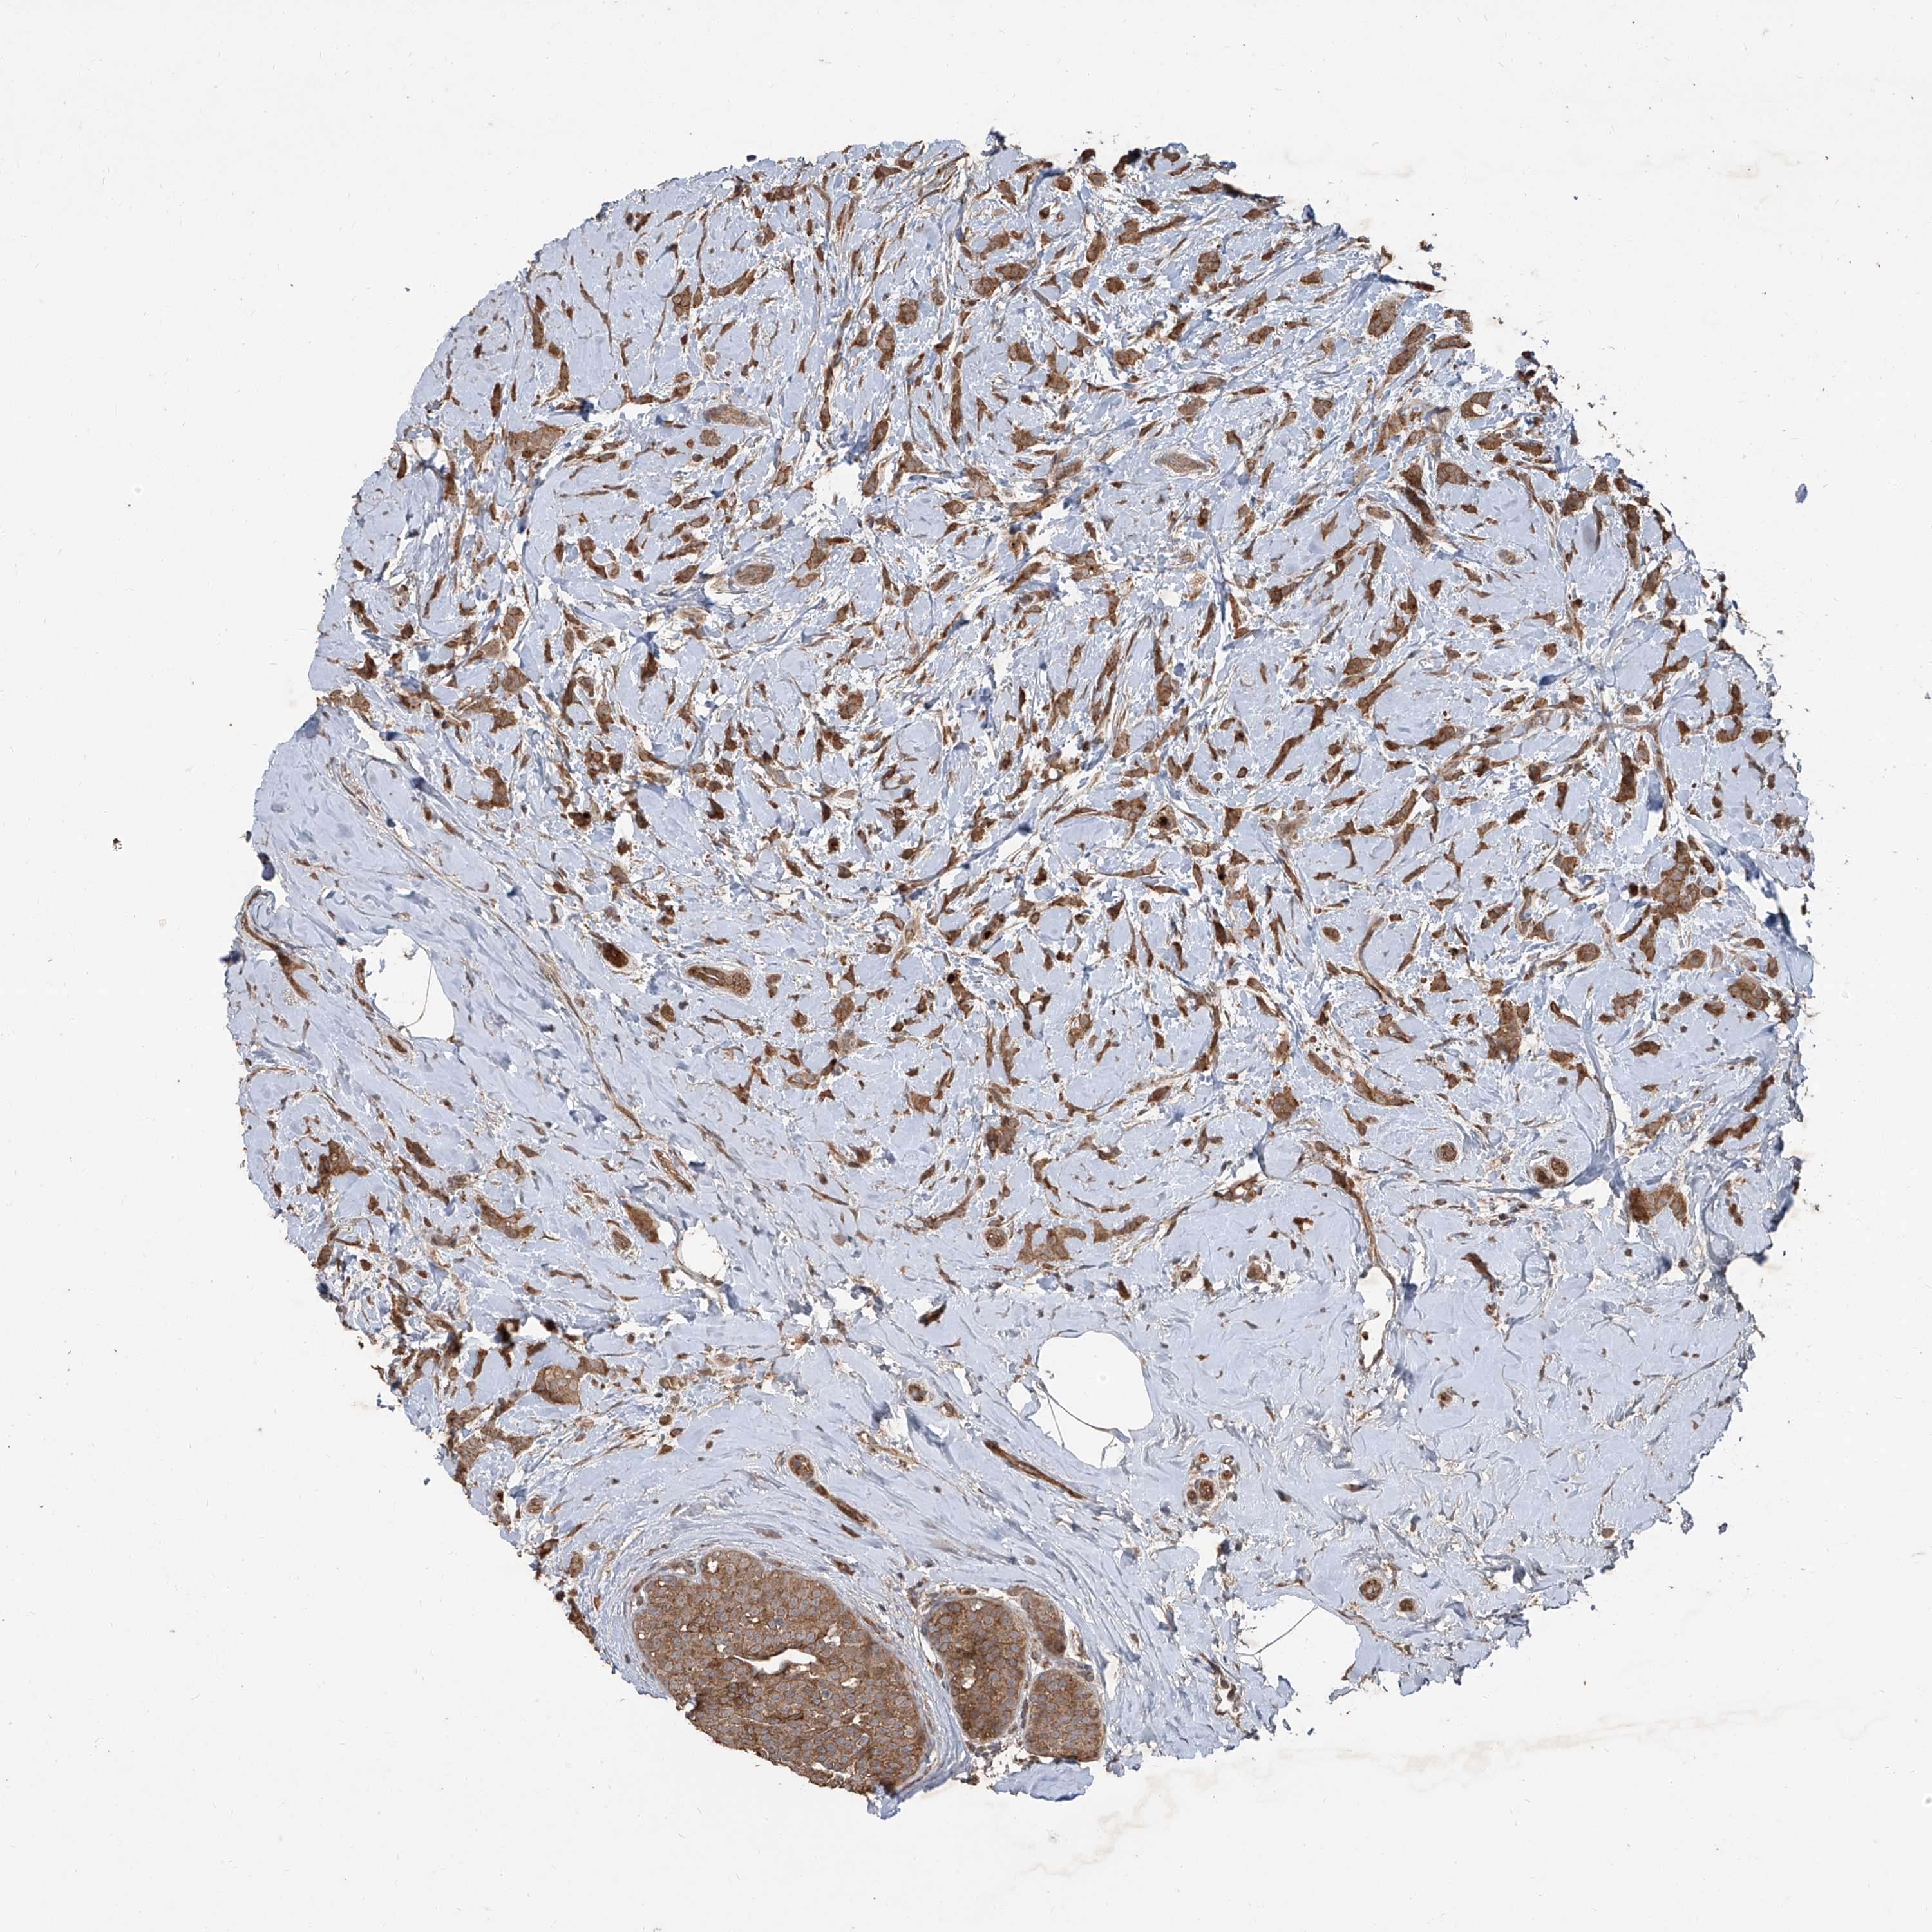

CANCER BREAST CANCER Show tissue menu

Breast cancer

Human cancer